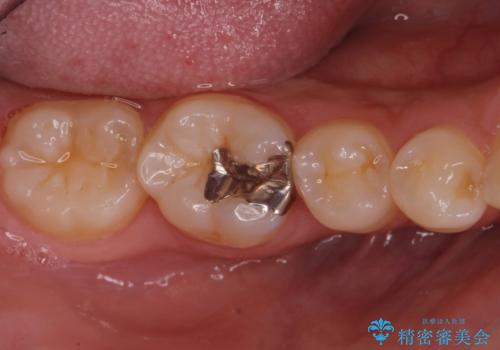

- 銀歯を無くしたいとの事で来院。

メタルを除去し、拡大鏡下で虫歯がない事を確認しe-maxインレーで治療を行いました。